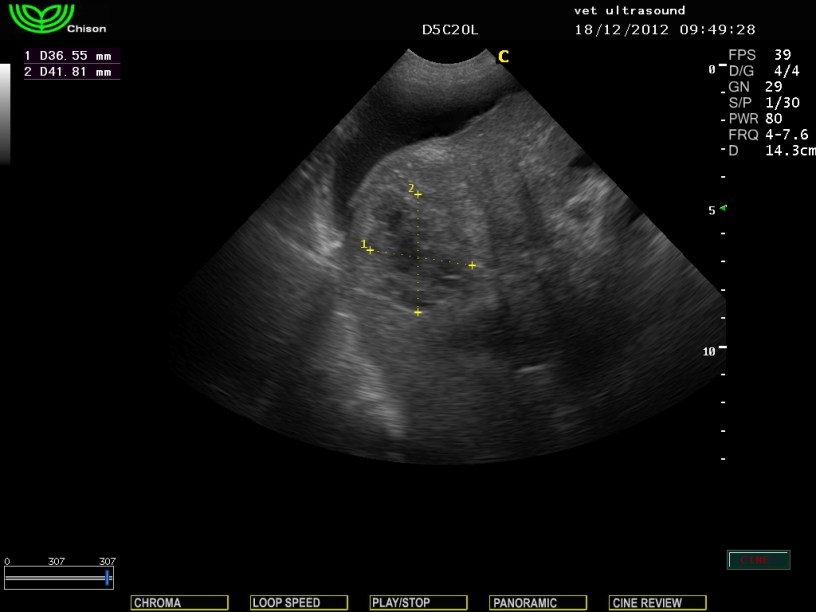

Υποηχογενείς αλλοιώσεις στους αριστερούς και διαφραγματικούς λοβούς του ήπατος και άφθονη παρουσία υγρού στη περιτοναική κοιλότητα.

Μετά από κυτταρολογική εξέταση του ασκιτικού υγρού βρέθηκαν κύτταρα συμβατά με την εικόνα του ηπατοκυτταρικού καρκινώματος.